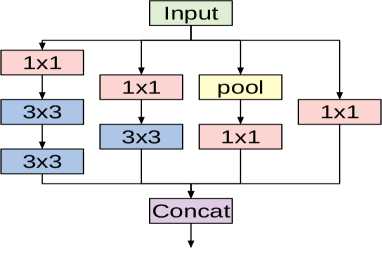

The fundamental building block for all Inception-style networks is the Inception module of which several forms exist. Figure 2 shows one variant of the Inception module that is used in the Inception V3 model. The module accepts an input and then branches into four different paths each performing a specific set of operations. The input passes through convolutional layers with different kernel sizes ( and ) as well as a pooling operation. Applying different kernel sizes allows the module to capture complex patterns at different scales. The outputs of all branches are concatenated channel-wise.

The overall architecture of the Inception V3 network is composed of conventional convolutional layers at the early stages of the network, where some of these layers are followed by max-pooling operations. Subsequently a stack of various Inception modules is applied. These modules have different designs with respect to the number of applied filters, filter sizes, depth of the module after symmetric or asymmetric factorization of larger convolutions, and when to expand the filter bank outputs. The last Inception module is followed by an average-pooling operation and a fully connected layer.